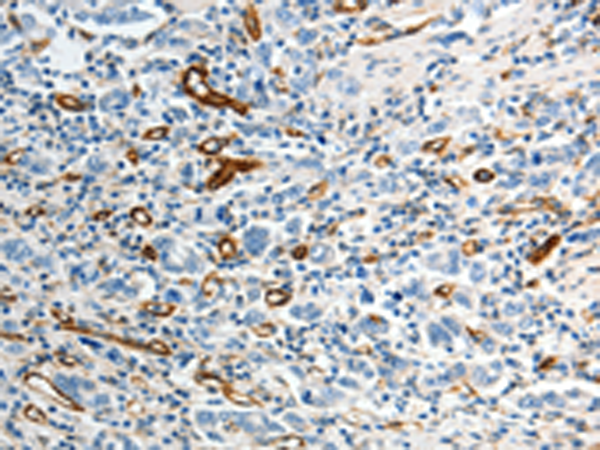

分类: 科研抗体货号: P04280别名: AT2; ATGR2; MRX88应用: IHC反应种属: Human, Mouse, Rat